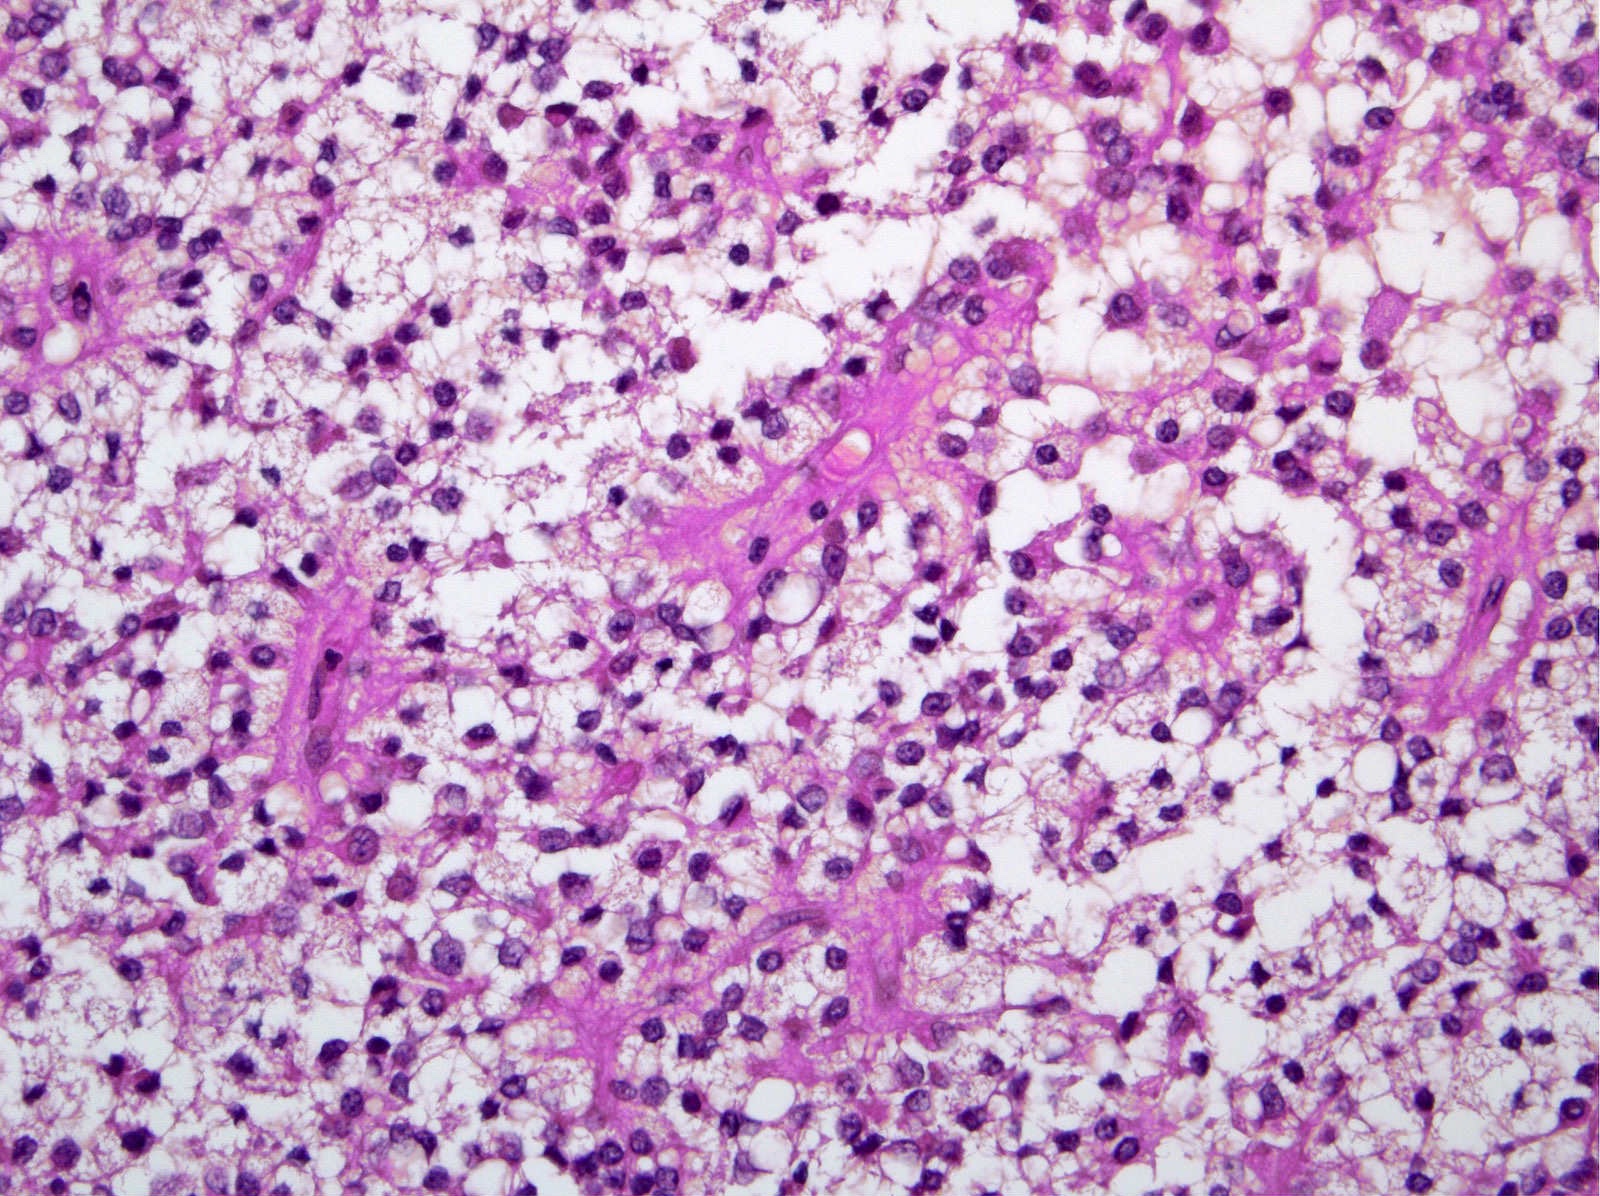

Microscopic (histologic) description

- Tumors are heterogeneous, with variable admixture of solid and pseudopapillary areas

- Solid areas are comprised of uniform cells admixed with capillary sized blood vessels

- Pseudopapillae are formed due to tumor cells getting detached from blood vessels forming fibrovascular stalks or rosette-like structures (Arch Pathol Lab Med 2020;144:829)

- Stroma usually shows various degrees of hyalinization or evidence of degeneration, such as hemorrhage, foamy macrophages, calcification and cholesterol clefts

- Tumor cells usually have a moderate amount of eosinophilic cytoplasm with intracytoplasmic hyaline globules (PAS+ and diastase resistant, positive for alpha-1-antitrypsin) and perinuclear vacuoles (Am J Surg Pathol 2011;35:981)

- Relatively uniform nuclei with finely textured chromatin, inconspicuous nucleoli and characteristic longitudinal grooves

- Variants include clear cell, oncocytic and pleomorphic

- Rare mitotic figures

- Although grossly well circumscribed, microscopic finding of infiltration to the surrounding pancreatic tissue is not uncommon

- Rare cases of highly aggressive behavior; histological features in those cases included diffuse growth pattern, extensive necrosis, significant nuclear atypia, high mitotic count (35 - 70/50 high power fields) or sarcomatoid features (Am J Surg Pathol 2005;29:512)

Microscopic (histologic) images

Contributed by Monika Vyas, M.D., Omid Savari, M.D. and Raul S. Gonzalez, M.D.